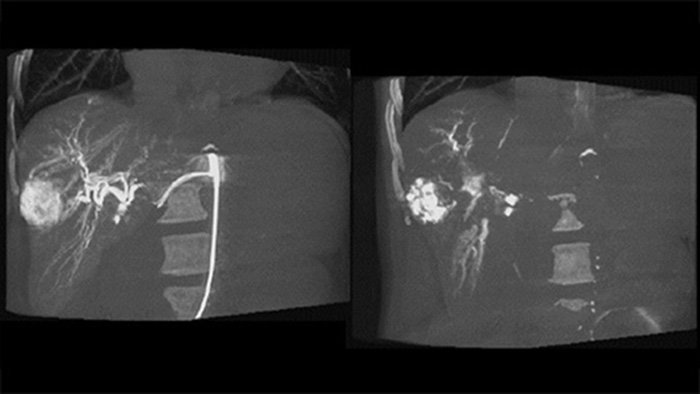

Полученные 3D-данные после эмболизации наглядно демонстрируют депонирование в опухоли эмболического материала, такого как Липиодол или рентгеноконтрастные гранулы5.

Функция Dual View обеспечивает одновременную визуализацию 3D-изображения артериальной фазы до эмболизации и изображения после эмболизации для наглядной оценки результата процедуры.